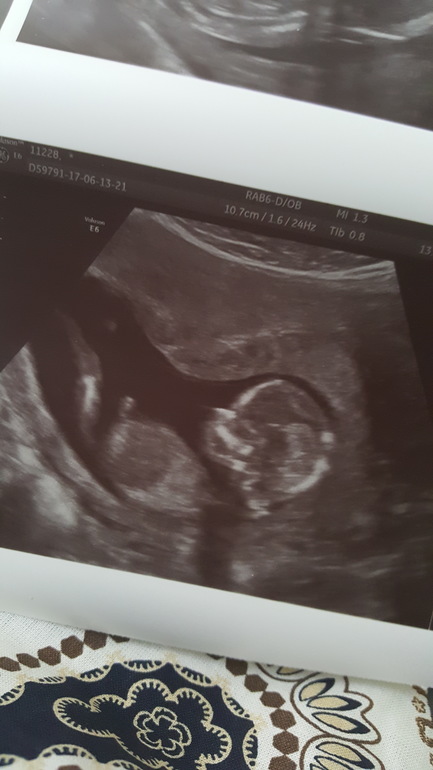

Узи 14 недель (13,3 по М)

Итак сходили сегодня на узи к врачу моему. Естественно она все опровергла, что мне намерил врач узи в пятницу (9.06).

Хорион (его уже пишут как плаценту) также остался 16мм.

Шейка не 31, а 39!!!! Как мне украли 8мм ума не приложу.

Померили нас сегодня основательно аж на 1,5 листах с обоих сторон. Так как мы по сроку уже 14 недель...узи уже 2 триместра.

Ктр не мерили, мерили вес....и так мы приблизительно - 100 грамм!

Еще раз подтвердили девочку!

Наши фото